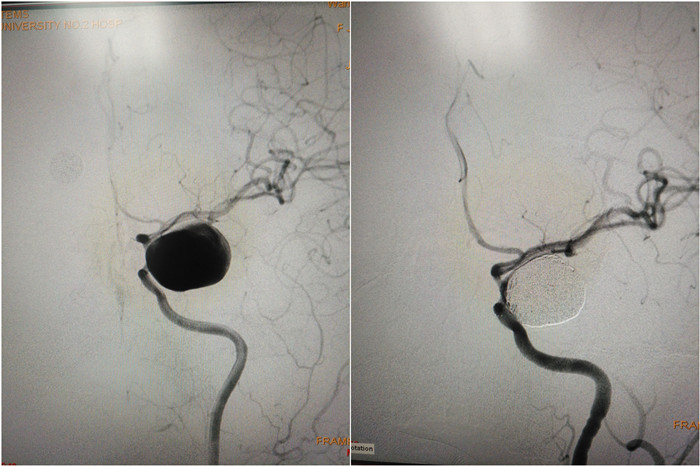

患者王女士因反复头晕行头颅核磁检查,发现颅内动脉瘤样病变,遂入住我院神经外科,经脑血管造影确诊为颈内动脉床突段巨大动脉瘤,大小约22*27mm。颅内动脉瘤被称为不定时炸弹,一旦爆裂,致死率和致残率极高。巨大动脉瘤尤其易发生破裂出血。曲友直教授团队经过缜密的分析和讨论,为患者制定了支架辅助动脉瘤栓塞的治疗方案,经过充分的术前准备,于1月24日在全麻下为患者实施了动脉瘤介入栓塞治疗,手术过程有条不紊,导管导丝应用娴熟,支架顺利到位释放,数枚弹簧圈致密填塞瘤腔,手术仅用时2个小时,既保持了载瘤动脉的通畅,又治愈了巨大动脉瘤,为患者拆除了这枚脑内“巨型炸弹。 ”